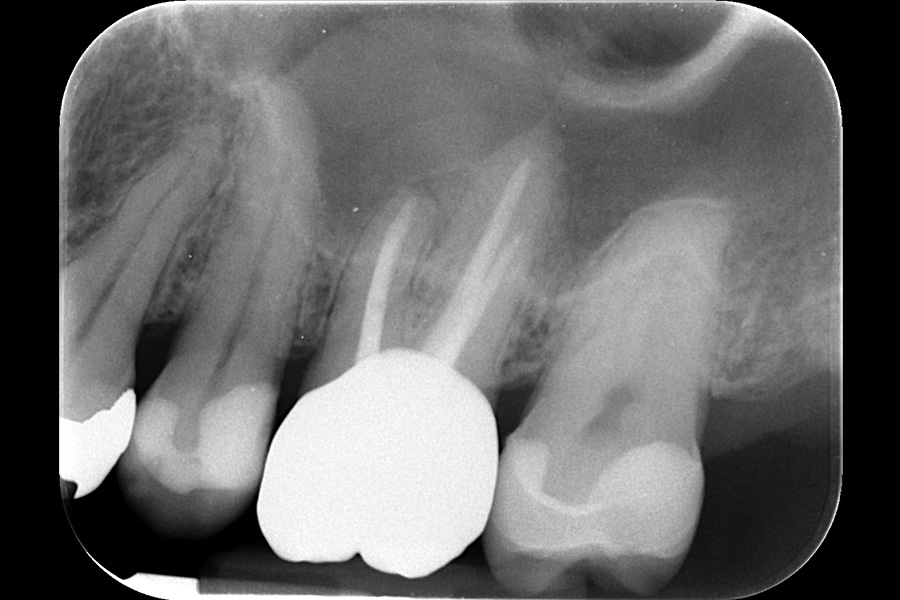

治療後